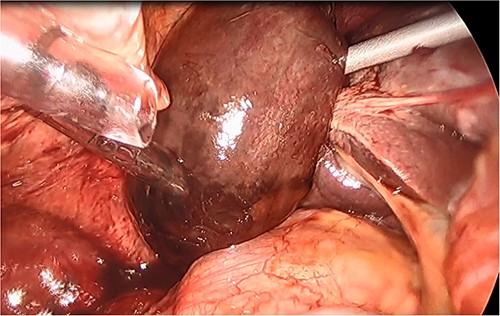

She had a good functional baseline, living in home independently and following anaesthetic review; after a family discussion, the consensus was to proceed to surgery. She underwent a laparoscopic cholecystectomy, and intraoperatively, the diagnosis of gallbladder volvulus was confirmed. A distended gangrenous gallbladder was found, which had undergone 360° clockwise rotation about the cystic duct (Figs 2, 3). The gallbladder was detorted to facilitate a traditional dissection of Calot’s triangle, achieving the critical view of safety (Figs 4, 5). The cystic duct was able to be cannulated facilitating an intraoperative cholangiogram which was unremarkable (Fig. 6). The gallbladder was then removed, and operation was completed without any complications. The histopathology of the gallbladder found diffuse haemorrhagic necrosis of the gallbladder without any evidence of dysplasia or malignancy. No cholelithiasis was present.

Intraoperative picture of the gangrenous gallbladder narrowing upon the torted pedicle; the cystic duct and artery.